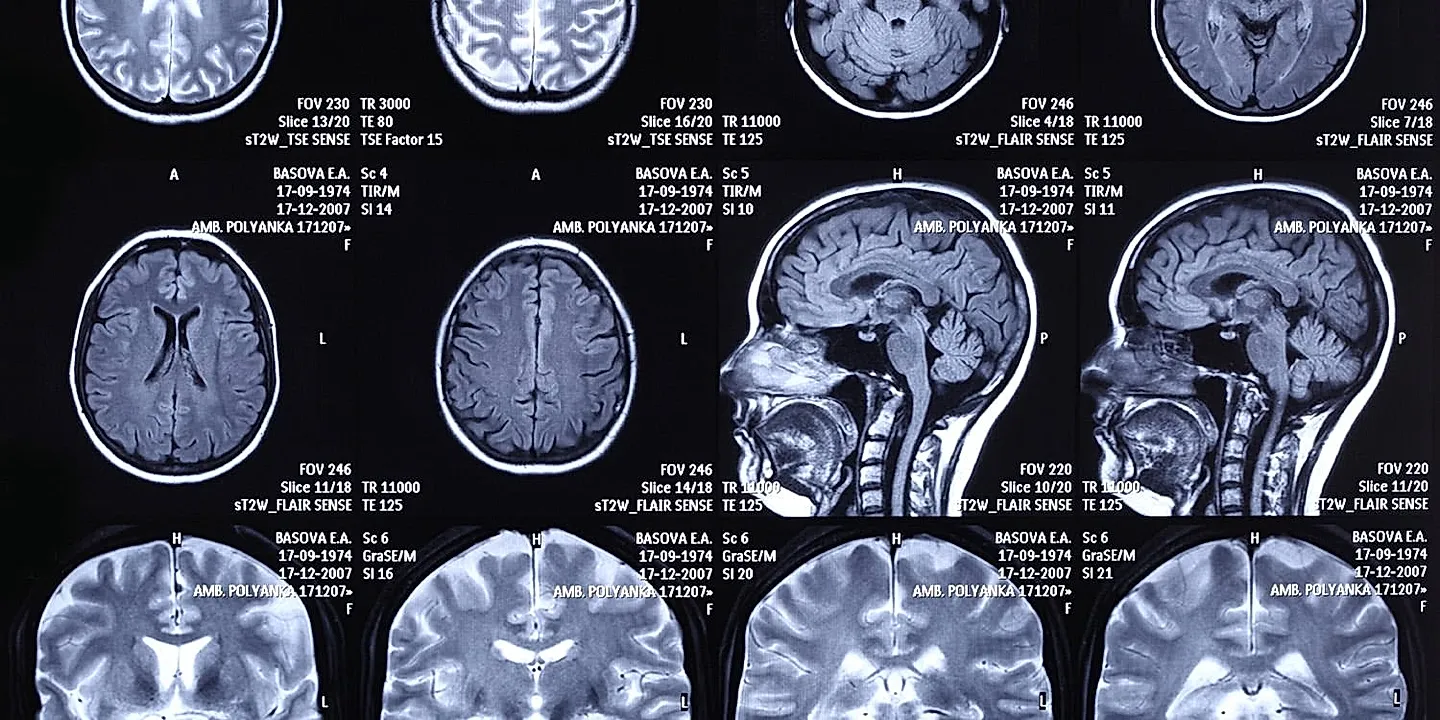

Испытуемых поместили в аппарат функциональной МРТ — технологии, позволяющей отслеживать активность мозга по изменению уровня кислорода в крови. Находясь в аппарате, участники должны были совершить реальные покупки: им выдавали 50 долларов, и одно из выбранных товаров они действительно забирали домой.